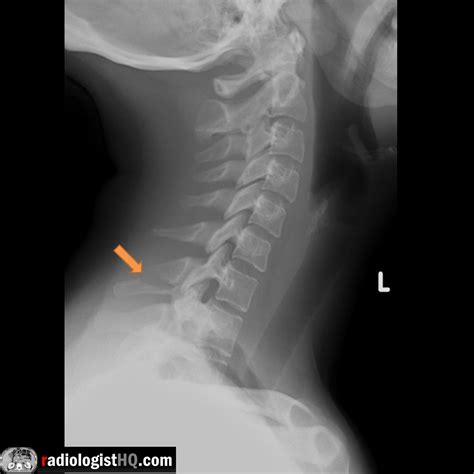

Diagnosis of Clay Shoveler's Fracture

Diagnosing a Clay Shoveler's Fracture involves a combination of physical examination and imaging tests. The diagnostic process typically includes:

• Imaging Tests:

• X-rays: To visualize the fracture and assess the extent of the injury.

• CT Scans: For a more detailed view of the bone structure and to rule out other injuries.